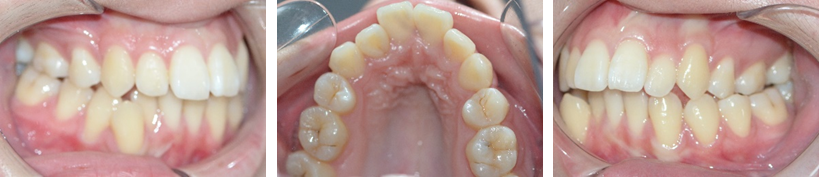

多次辗转求医后,她来到了徐州市口腔医院正颌正畸中心。经过详细检查和CBCT影像分析,最终诊断为“上颌骨发育不足、II类错合畸形、睡眠呼吸暂停综合征”。这意味着,她需要的不仅是美观上的改善,更是功能上的重建。

我院正颌外科团队为李女士制定了个性化方案:通过腭中缝骨皮质劈开术解除上颌骨阻力,联合上颌骨牵张成骨术让骨骼重新扩展,如同迎来“第二次发育”。治疗过程全程采用口内操作,无外部疤痕,最大程度保护组织并缩短恢复时间。